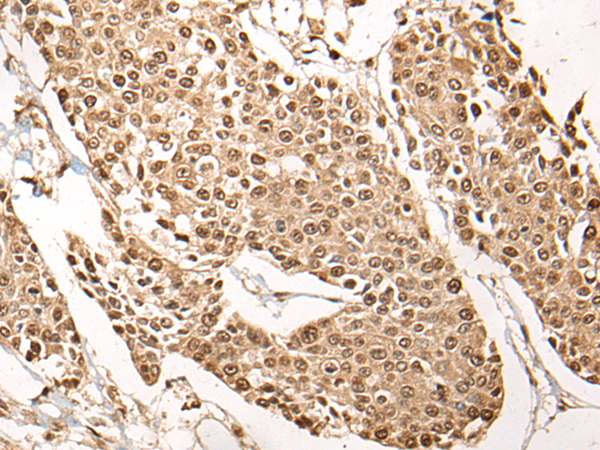

分类: 科研抗体货号: P06989别名: CPP32; SCA-1; CPP32B应用: WB,IHC反应种属: Human, Mouse, Rat